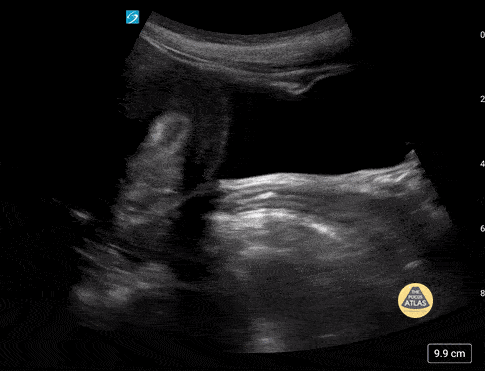

Peds-Genitourinary - Normal Adolescent Uterus

Normal adolescent uterus. Contributor: Paul Khalil, MD Nicklaus Children's Hospital @khalil3paul